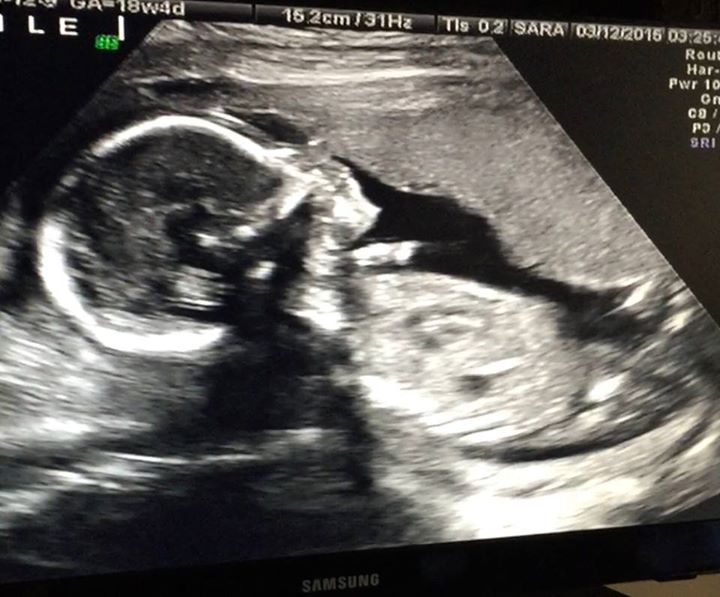

婴儿影像(图:力克胡哲脸书)

3月16日,天生没有四肢的布道家力克胡哲于脸书兴奋的宣布,妻子宫原佳苗所怀的第二胎是个男孩。随后更是贴出了超声波扫描影像,婴孩的头、鼻子、身体已经清晰可见。